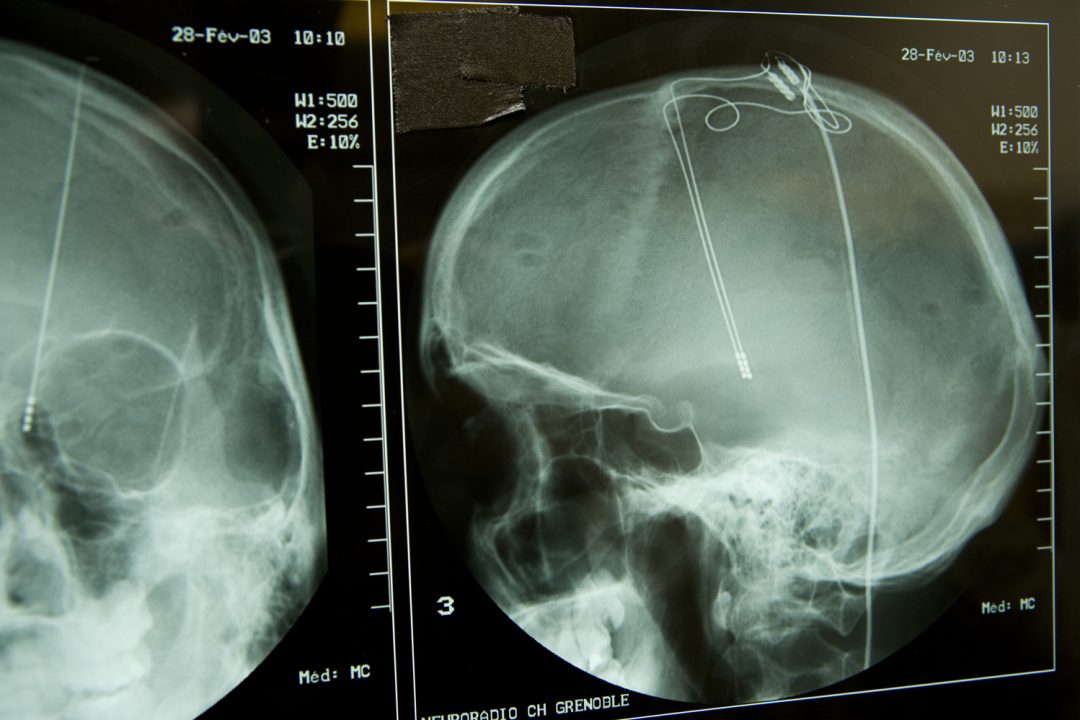

However, studying how brain networks interact with each other is complicated. Brain networks can be explored by delivering brief pulses of electrical current in one area of a patient’s brain while measuring voltage responses in other areas. In principle, one should be able to infer the structure of brain networks from these data. However, with real-world data, the problem is difficult because the recorded signals are complex, and a limited amount of measurements can be made.

In a study published in PLOS Computational Biology, a patient with a brain tumor underwent placement of an electrocorticographic electrode array to locate seizures and map brain function before a tumor was removed. Every electrode interaction resulted in hundreds to thousands of time points to be studied using the new algorithm.